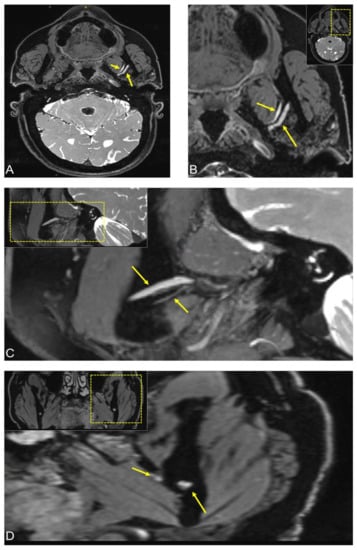

2.2. Case 2